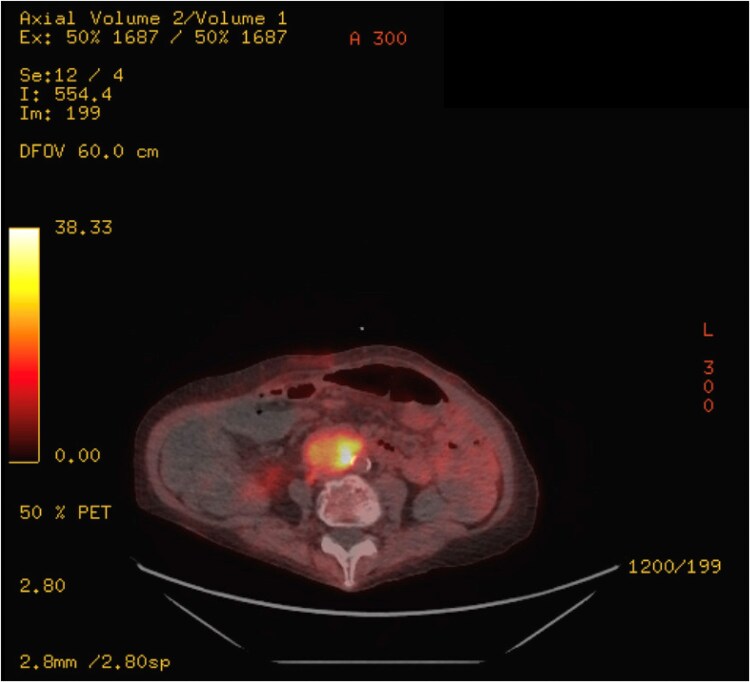

A paraganglioma is a neuroendocrine tumor classically associated with catecholamine production. We describe a 71-year-old woman with an incidentally identified para-aortic mass who later developed hyperglycemia, hypertension, hypokalemia, and leukocytosis. Work-up ultimately revealed significantly elevated adrenocorticotropin (ACTH), cortisol, and metanephrines, and biopsy of the mass suggested paraganglioma cosecretion of both ACTH and catecholamines. Using osilodrostat to decrease her excess cortisol production, she underwent successful surgical paraganglioma resection. Pathology of the mass demonstrated a paraganglioma with ACTH-producing cells, confirming the diagnosis of ectopic Cushing syndrome (CS). Following resection, the patient had resolution of hypertension and hyperglycemia and normalization of the hypothalamic-pituitary-adrenal axis. We describe the work-up and important perioperative and long-term management considerations for patients with hypercortisolism from ectopic CS and catecholamine excess.